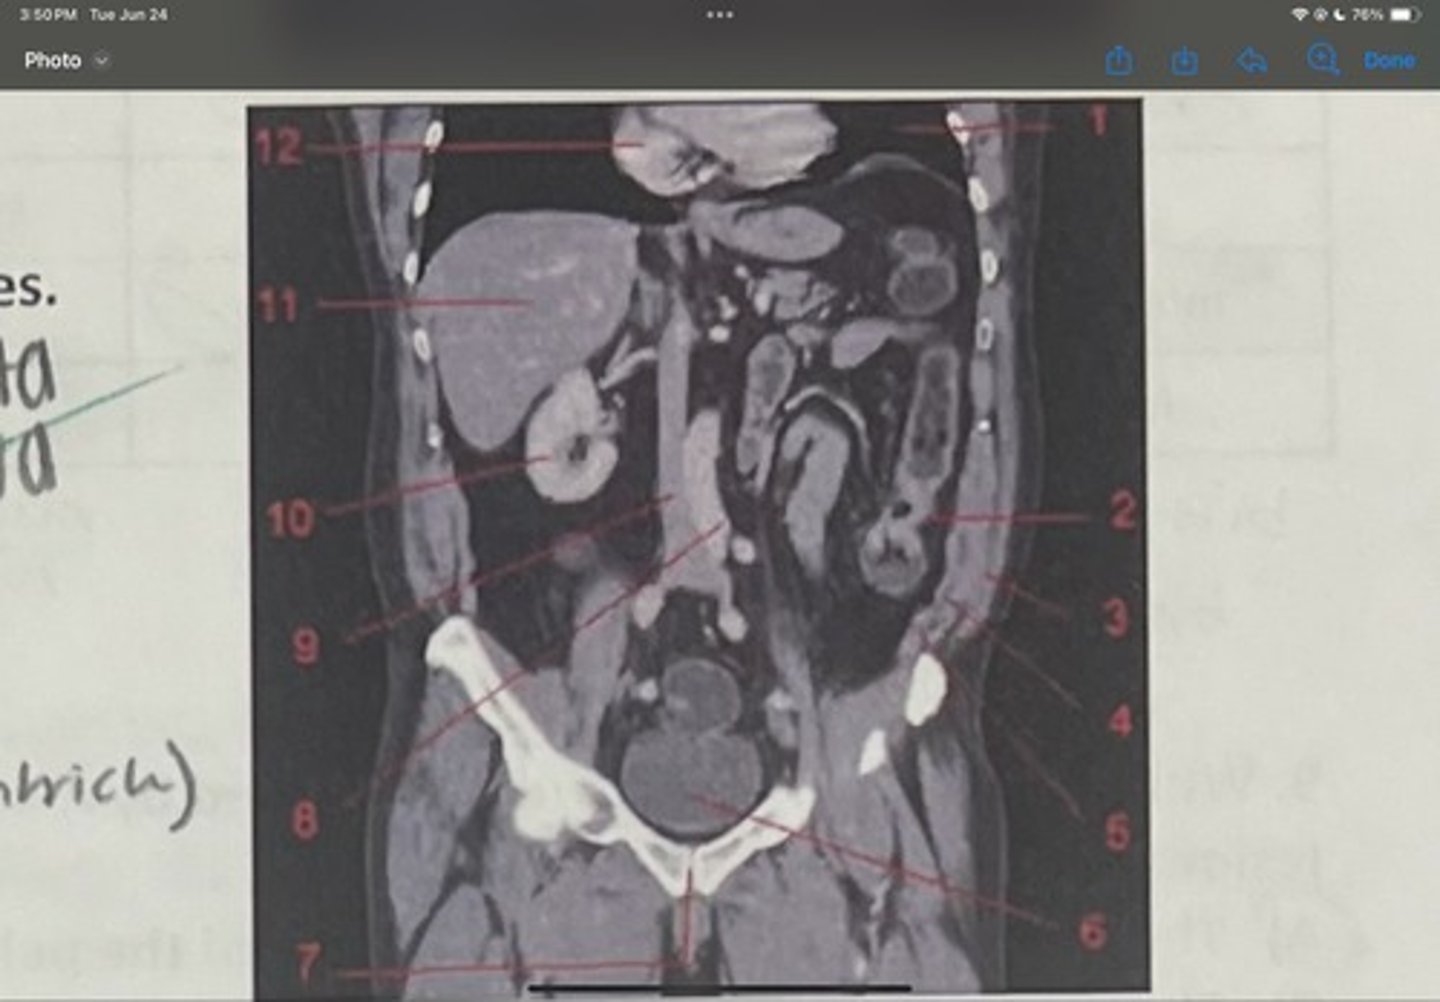

What is 1

Descending colon

What is 2

External oblique

What is 3

Internal obliques

What is 4

Transversus abdominis

What is 5

Bladder

What is 6

Pubic sysmphysis

What is 7

Abdominal aorta

What is 8

Inferior vena cava

What is 9

Right kidney

What is 10

Liver

What is 11

Heart (right ventricle)

What is 12

Subcostal nerve (T12)